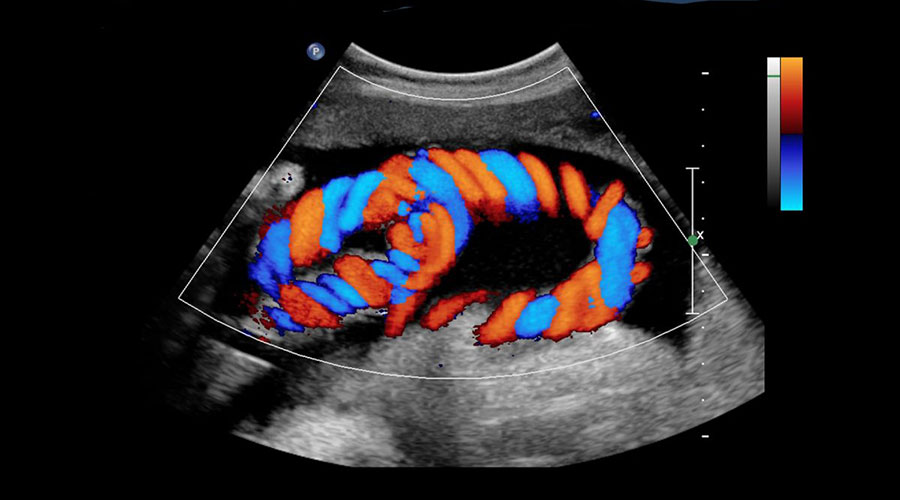

Color doppler, one of the ultrasound imaging techniques, is used to detect blood flow in the vessels and to image organs within the body using high-frequency sound waves. First, sound waves are sent through the probe. Likewise, the returning sound waves are collected by the probe and converted into electrical energy. It is also converted into an image by computer. It is used in the examination of many parts of the body. The main areas of use are; It can be summarized as intra-abdominal organs, superficial organs such as thyroid gland, breast, pregnancy follow-up, heart, arteries and veins.

In our center, ultrasonography devices with the technology developed by GE (Logic 9) and Siemens (Antares, Sequia) companies between 2003 and 2005 are used and their up-grades are carried out continuously. Many early-stage diseases that were not seen before can be diagnosed and treated. Thanks to its high resolution, it facilitates US-guided biopsy and directs the treatment.